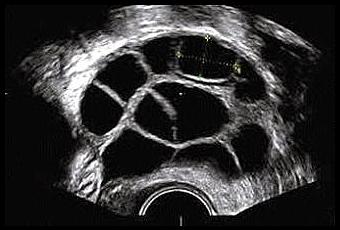

La reserva ovárica de una mujer puede estimarse mediante el análisis en sangre de ciertas hormonas. Un valor elevado de la hormona FSH (más de 10-12mUI/ml) entre el tercer y quinto día del ciclo menstrual indica una reserva ovárica reducida.

La hormona Antimulleriana también es indicadora de reserva ovárica y puede ser analizada en cualquier momento del ciclo, punto beneficioso en los estudios de fertilidad frente a la FSH.